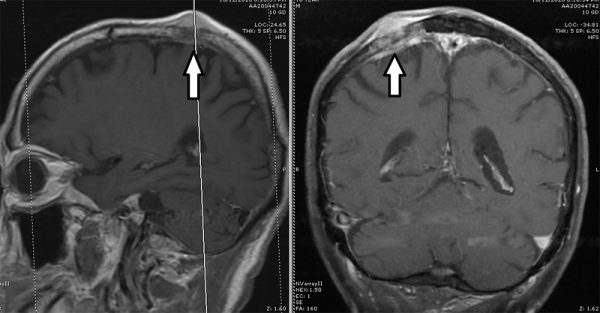

肺癌转移脑颅骨(箭头处)。

医生怀疑是肺癌转移脑部,遂安排廖大叔进行)。在放射性核素扫描下,确定廖大叔的颅骨内有水肿和膨胀现象,连带脑膜也肿了起来,而造成此现象的可能性只有一个,那就是脑颅骨转移。

我用了立体定向开颅术,在廖大叔的头颅上切除了5公分乘6公分、厚度25毫米的颅盖,把肿瘤细胞、脑膜和病变组织完全切除干净,之后,再以钛镁重建颅骨和脑膜。